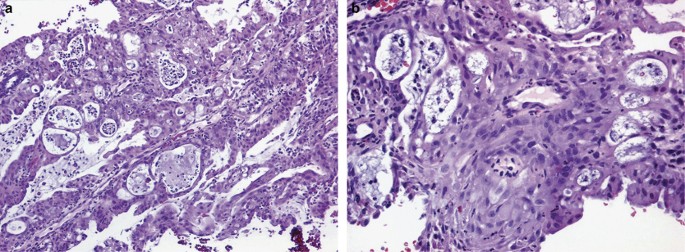

Cytoplasmic clearing in ECa can be secondary to the following: (1) glycogen-rich squamous component; (2) sub- or supranuclear vacuoles (secretory); (3) clear cell changes, not otherwise specified (NOS; undetermined nature); and (4) artifact. In ECas with glycogen-rich squamous differentiation, the cells are either polygonal or rounded and are typically seen with conventional areas of squamous differentiation (Figure 14a and b). ECas with secretory change are characterized by the presence of supra and/or subnuclear glycogen vacuoles (Figure 15a and b). Diffuse secretory changes are commonly seen in tumors of postmenopausal patients, although they can also be seen in reproductive-age women and in patients treated with progestins.

ECas can also have clear cytoplasm that do not fall into the categories described above, and these are designated as clear cell changes, NOS (Figure 16). Lastly, clear cells may be seen on the surface of ECa or on the edges of the tumor sections and this is most likely to be degenerative/artifactual in nature (Figure 17).

Overall, ECas with secretory changes are most likely to be confused with a clear cell carcinoma. The latter is diagnosed not by the presence of clear cells but by a combination of the typical architectural patterns (tubulocystic, papillary, and solid). Furthermore, cells range from cuboidal to low columnar, to polyhedral to flattened (Figure 18a–c), which is in contrast to ECas with secretory change that are almost exclusively composed of a uniform population of columnar cells. Cytologic atypia is often more striking in clear cell carcinomas. Immunohistochemistry may be of value in this differential diagnosis. As ECa with clear cells is typically of low grade, it shows diffuse and strong ER and PR expression in contrast to clear cell carcinoma (usually negative or weakly positive). p16 is diffusely positive in 50% of clear cell carcinomas, whereas it is patchy in ECa with clear cell changes. Napsin A and p504s have been shown to be more specific in the diagnosis of clear cell carcinoma compared with HNF-1β, as the latter is frequently positive in ECas with and without clear cells (Figure 19a–c).35, 48, 49, 50, 51, 52